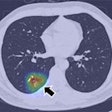

As a result, the group sought to investigate how the depth of CNNs affects performance in detecting and classifying focal lesions in medical images. Three different tasks in medical imaging were evaluated: detecting lung nodules on CT, classifying lung nodules as benign or malignant on CT, and detecting polyps on CT colonography. After extensive experiments, the researchers found that CNNs with three or four convolutional layers were more effective than shallower architectures. However, using deeper architectures did not yield further improvements in performance, Suzuki said.

"CNNs with three or four convolutional layers might be adequate for focal lesion detection and classification in CT," he told AuntMinnie.com. "Thus, the use of an unnecessarily deeper deep-learning model should require an unnecessarily larger number of training cases and would result in inferior performance."